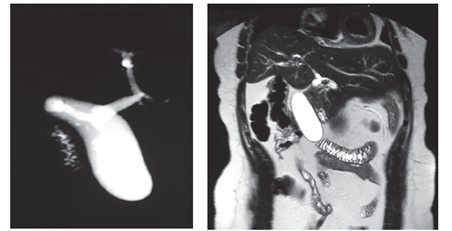

Antes de su reingreso, ante la sospecha clínica de colecistitis aguda no litiásica o pancreatitis aguda biliar se ordenaron estudios de tomografía computarizada (TC) abdominal con contraste, la cual reportó vesícula en epigastrio, subhepática, izquierda (figura 6).

Durante la hospitalización se practicó colangiorresonancia magnética, en la que se confirmó vólvulo de la vesícula biliar y disminución del flujo sanguíneo en su pared. Por el empeoramiento de su dolor abdominal, 10/10 en la escala análoga, se ordenó colecistectomía urgente por laparoscopia, la cual fue convertida por malrotación intestinal incompleta (ciego y apéndice en el hipocondrio izquierdo de tipo III de Stringer, plastrón vesicular y distorsión de la anatomía) (figuras 6 a 7). Se corrigió el vólvulo y se hizo colecistectomía. La evolución posoperatoria fue satisfactoria.

En general, el diagnóstico prequirúrgico es casi imposible en primera instancia, de ahí que se somete a cirugía como abdomen agudo, en la que se practica laparotomía exploratoria. Solo se llega a esta si se tiene alta sospecha a partir de la historia clínica del paciente y de las ayudas imagenológicas como sucedió en estos dos casos, luego de múltiples estudios previos, distensión vesicular reportada por ecografía, ubicación heterotópica de la vesícula revelada en la TC y rotación del hilio en la colangiorresonancia magnética que orientaron hacia el diagnóstico de torsión de la vesícula biliar (figuras 1, 2, 6 y 7).

Debido a la dificultad para llegar a un diagnóstico partiendo del deterioro del estado general, en el primer caso se inició el enfoque por el Servicio de Medicina Interna, para descartar la posibilidad de un tumor que estuviera deteriorando el estado general de la paciente, hecho que justificó los marcadores tumorales, los cuales se hallaron normales. Por otra parte, el uso de la tomografía computarizada abdominal con contraste, la ecografía abdominal y la colangiorresonancia magnética -más sensible y específica para el caso que nos ocupa- reveló detalles precisos del cuello de la vesícula biliar e isquemia de la pared 2 (figura 7) y permitió determinar la posición inadecuada de dicho órgano.